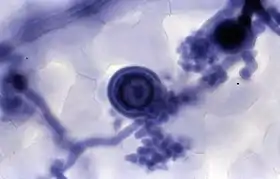

El azul de tripano, azul de tripán o azul tripán es un colorante azoico que se utiliza en tinciones histológicas[2] para ensayos de viabilidad que permiten diferenciar células vivas de células muertas. Las células vivas o tejidos con la membrana celular intacta no se colorean debido a que la membrana celular es selectiva respecto a qué compuestos pueden atravesarla. En las células viables, con membrana intacta, no se incorpora el azul de tripano; por el contrario, sí atraviesa la membrana de las células muertas. Por lo tanto, las células muertas se muestran de un distintivo color azul bajo el microscopio (típicamente, empleando una cámara de Neubauer para contarlas).[3] Debido a que las células vivas excluyen al colorante y no se tiñen, este método también se llama método de tinción por exclusión.

El azul de tripano se usa comúnmente en microscopía (para el recuento de células) y en ratones de laboratorio para la evaluación de la viabilidad de tejidos. El método no puede distinguir entre células necróticas y células muertas por apoptosis.